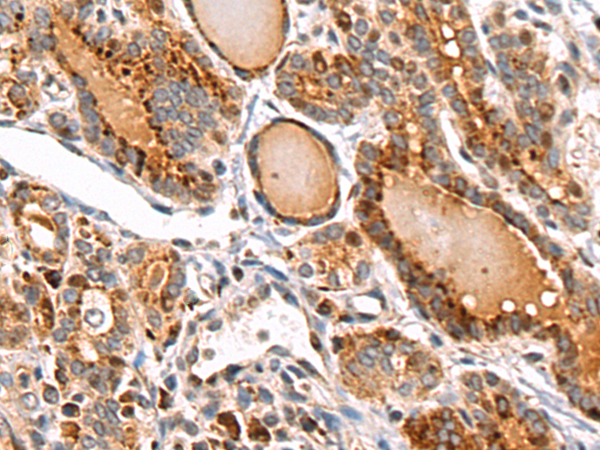

分类: 科研抗体货号: P10583别名: FXY2; RNF60; TRIM1; MRX101应用: IHC反应种属: Human, Mouse